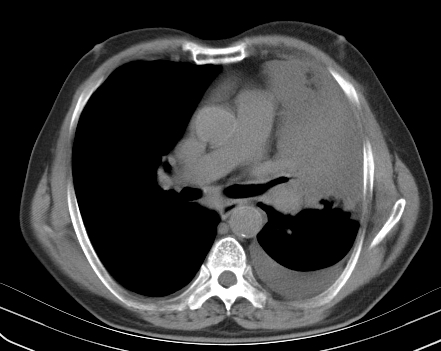

以下是引用老爱克斯新网客在2008-7-31 6:30:00的发言:[br]左肺上叶大片状病灶,左肺上叶支气管狭窄呈鼠尾状,左肺门增大,纵隔内见肿大淋巴结,左侧胸腔积液,余肺清晰。左肺中心型肺癌淋巴结转移,

以下是引用zjzjr在2008-7-31 8:45:00的发言:[br]考虑左侧中心性肺癌伴阻塞性肺炎,左肺上叶肺不张,纵隔淋巴结转移;左侧胸腔积液。建议行纤支镜检查。

以下是引用zjb在2008-7-31 6:32:00的发言:[br]左侧中心性肺癌 阻塞性肺炎 肺不张 胸腔积液 建议气管镜

以下是引用sdzyy在2008-7-31 8:47:00的发言:[br]病灶较治疗前有所进展,胸水增多, 左侧中心性肺癌 并 阻塞性肺炎 肺不张 胸腔积液 可能性大; 建议气管镜检查。 [br] [br]